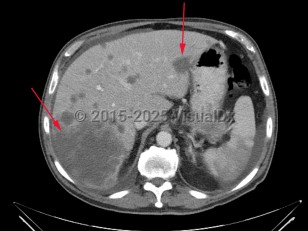

Liver cancerLiver cancer